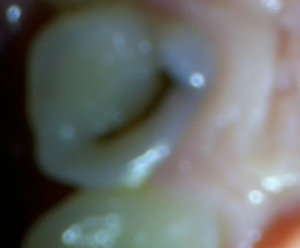

Второй вопрос: Мне вылечили от кариеса семнадцатый и двадцать шестой зубы. Лечение производилось от двух до трех недель назад. До этого жевать было удобно, как твердую, так и мягкую пищу. Сейчас есть мягкую пищу удобно и комфортно, а твердую - не очень. Болей нет, но ощущения не очень приятные. В районе семнадцатого и двадцать шестого, ощущается некий дискомфорт.

С чем это может быть связано?

На снимке в области семнадцатого и двадцать шестого зуба, под пломбой, наблюдается полость, которая неграмотно препарирована перед установкой пломбы, чувствительность и некий дискомфорт при надкусывании или пережевывании твердой пищи связано именно с этим. Что касается шестнадцатого зуба, я считаю, что полость имеется, но все-таки необходим еще и очный прием.